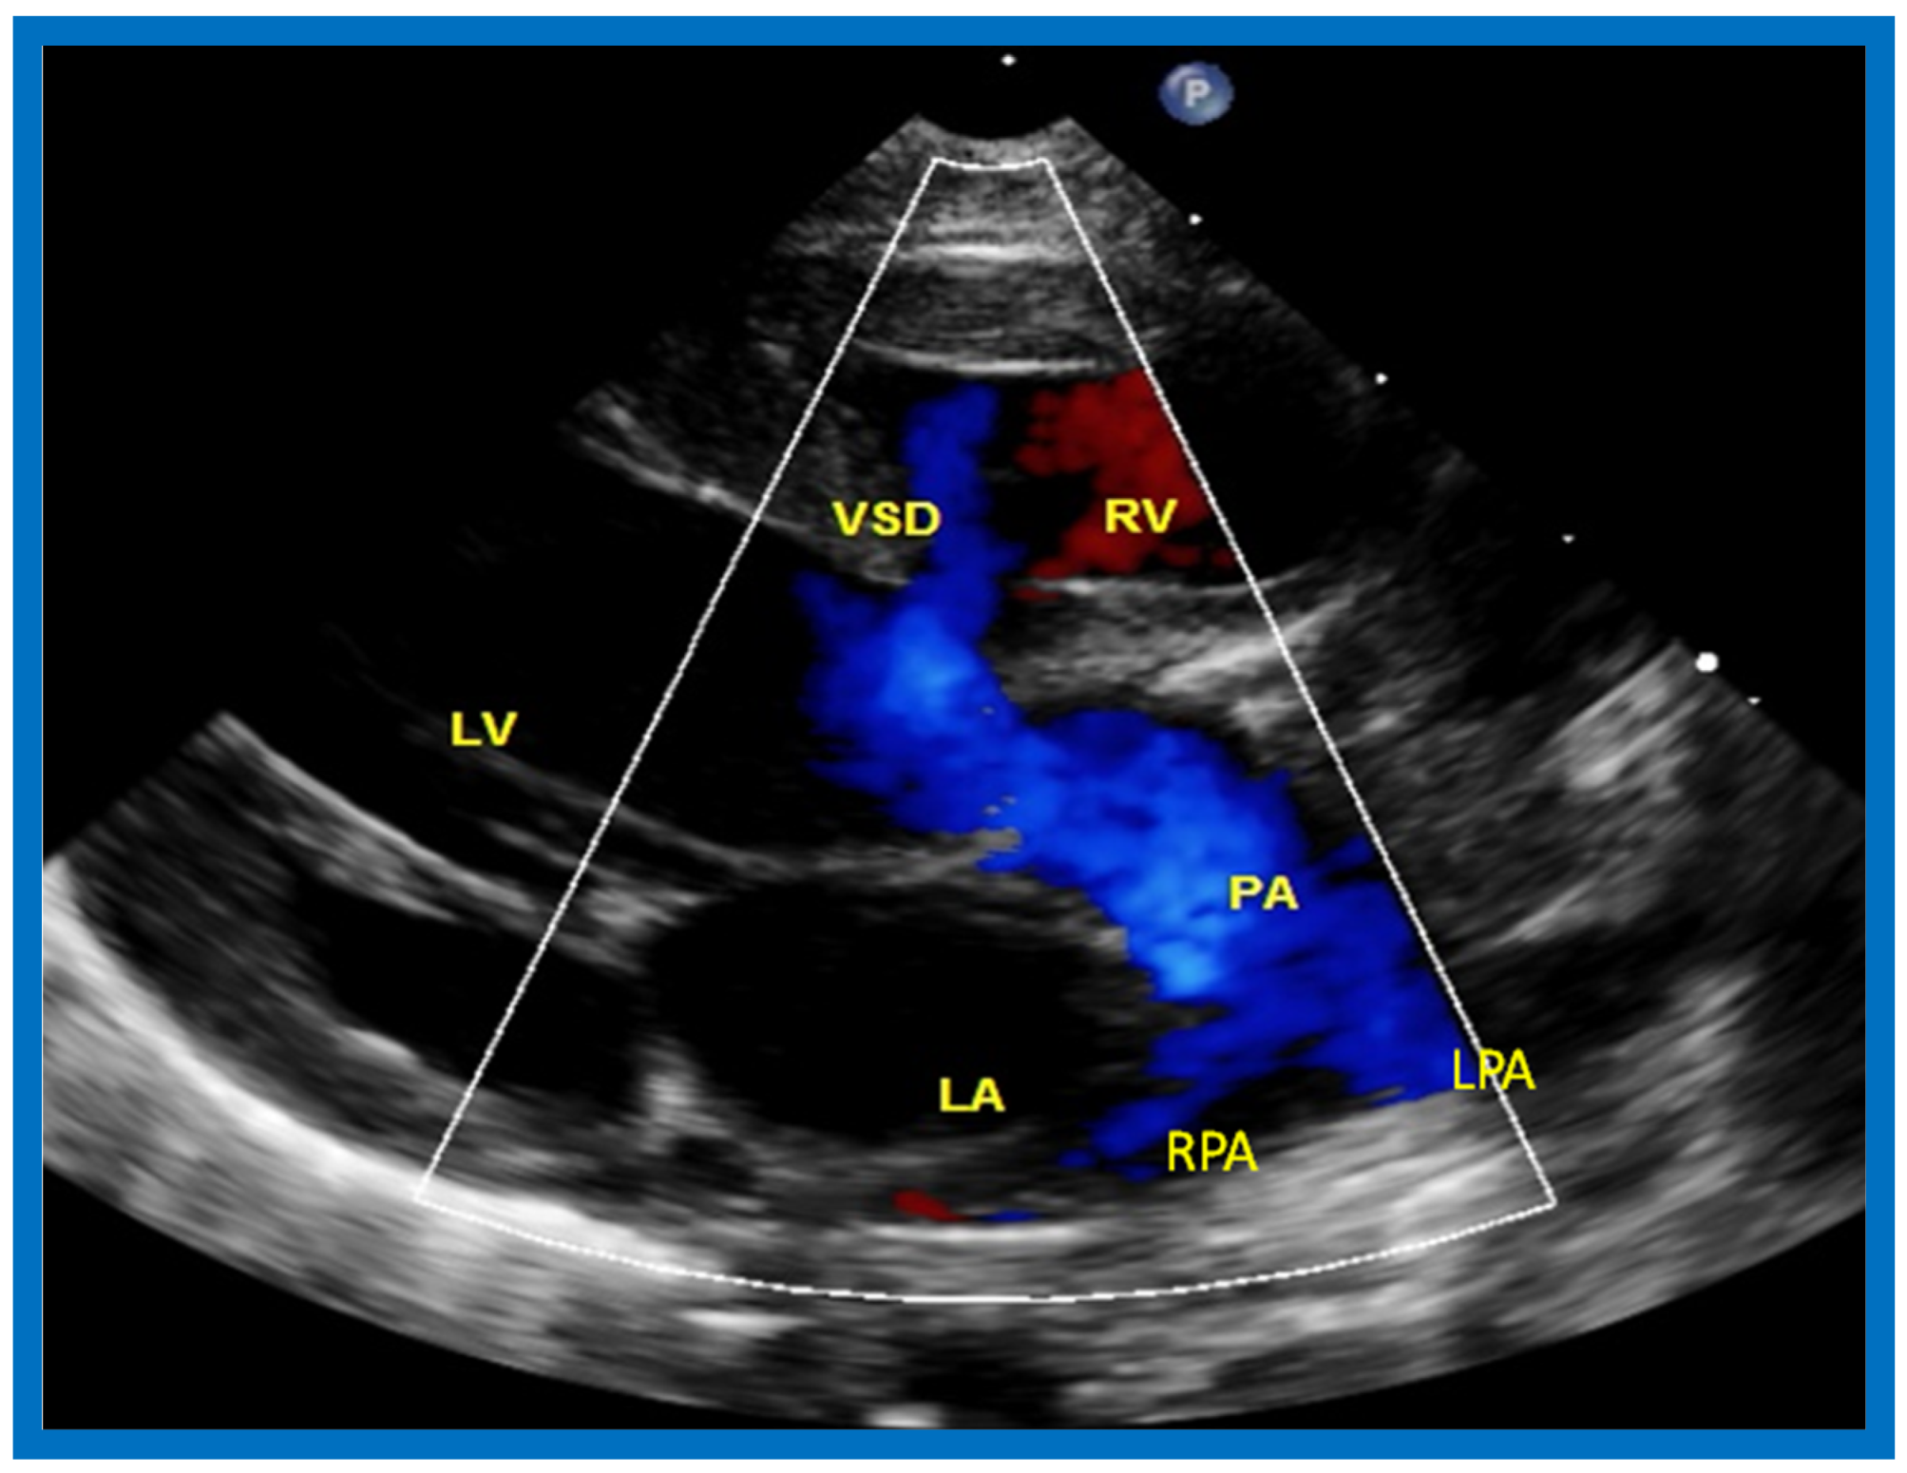

Figure 22.

Selected video frame from precordial long axis view with color flow mapping of another neonate with tricuspid atresia and transposition of the great arteries illustrates the left atrium (LA), left ventricle (LV), a small right ventricle (RV) and a moderate sized ventricular septal defect (VSD). The vessel coming off of the LV bifurcates into left (LPA) and right (RPA) pulmonary arteries. Reproduced from Rao P.S. [39].